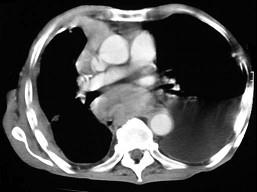

问题 67岁,男,呼吸急促3个月,请结合胸片选出最可能的诊断 ( ) [WXJ-01111.jpg ]

选项 A、肺癌 B、胸膜间皮瘤 C、胸膜肥厚 D、化脓性胸膜炎 E、包裹性胸腔积液

答案 B